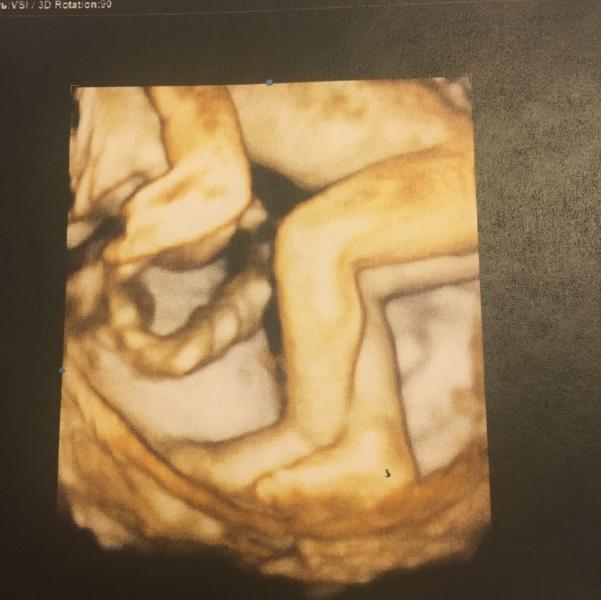

Вчера была на УЗИ в ЦИРе.✌🏻Меня одолели знакомые, утверждающие что в жк мне всего не скажут, надо идти платно и по рекомендации, а то ппц, рожу неведому зверушку🦄. Я сдалась🙋

Итак, 07/07 в 19.00 я приехала к Тё С.А (лучше него как мне сказали не найти), вырвался муж с работы, ему было так важно, что я даже удивилась, ведь за 6 лет с этим сухариком я такого не ждала🙈